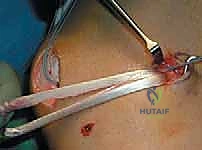

The retinaculum is incised longitudinally, slightly medial to the patellar border, to expose the torn edge of the ligament. The stump is carefully mobilized, freeing it from underlying capsular adhesions to ensure it can be advanced to the patellar footprint without excessive tension. The quality of the tissue is reassessed at this stage; it must be robust enough to hold high-strength suture.

Preparation of the patellar bed is a critical step for biologic healing. The native insertion site on the proximal two-thirds of the medial patellar facet is exposed. Using a curette, rongeur, or a high-speed burr, the medial cortical margin is lightly decorticated down to bleeding cancellous bone.

This bleeding bed provides the necessary marrow-derived mesenchymal stem cells and growth factors to facilitate robust ligament-to-bone healing. Two suture anchors (typically 4.75 mm or smaller, biocomposite or PEEK) double-loaded with ultra-high-molecular-weight polyethylene (UHMWPE) sutures are then placed into the decorticated patellar margin. The anchors are spaced appropriately (one proximal, one distal) to recreate the broad native footprint.

The sutures are then passed through the mobilized MPFL stump. A secure, tissue-gripping stitch configuration is mandatory to prevent pull-through. A Krackow stitch or a locking Mason-Allen configuration is placed using the limbs from both anchors, effectively grasping the robust fibrous tissue of the MPFL and the overlying VMO fascia.